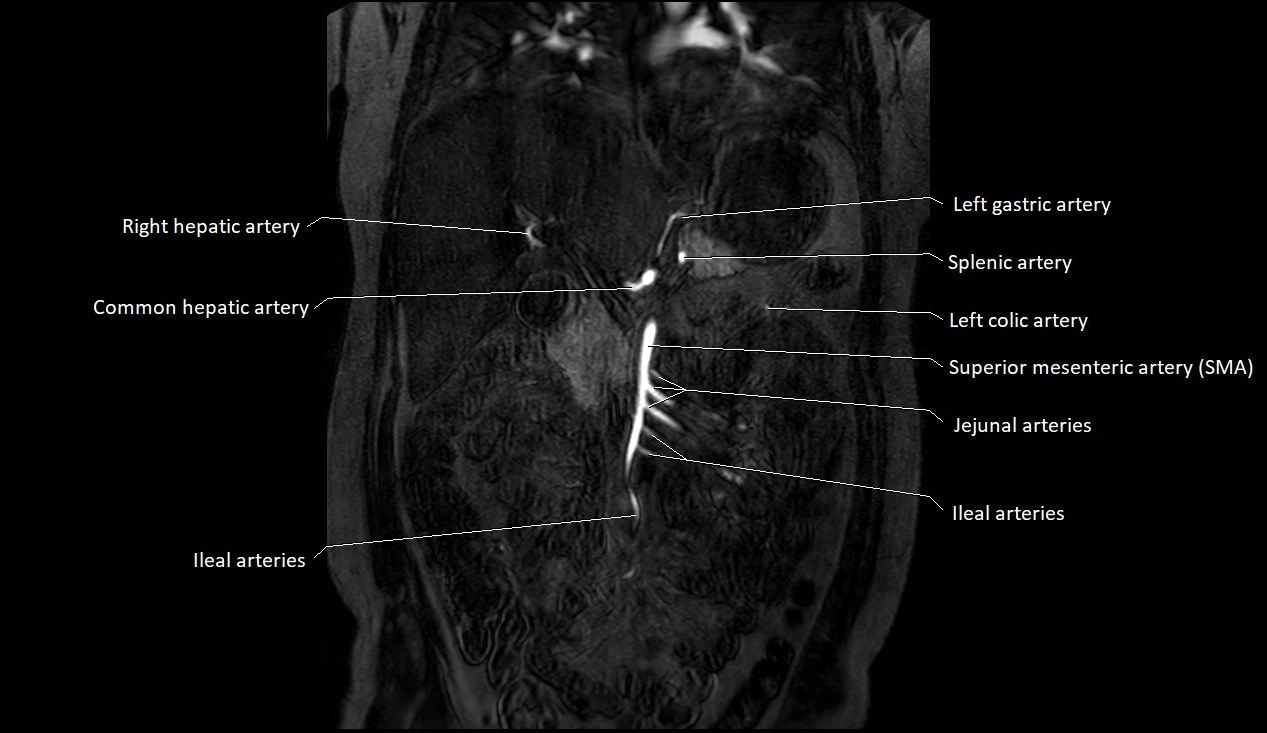

MRA (Magnetic Resonance Angiography):

• Contrast-enhanced MRA provides high-resolution imaging of the aorta and its branches

• Allows 3D reconstruction of visceral, parietal, and terminal branches

• Excellent for evaluating aneurysm size, dissection flap, stenosis, or preoperative planning

• Non-invasive alternative to conventional angiography

MRI images

image